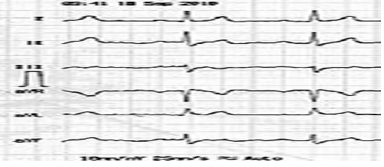

Paciente, sexo masculino, 45 anos de idade, sem patologias prévias, totalmente assintomático, sem histórico familiar positivo para quaisquer patologias cardiovasculares, foi ao médico, pois estava com uma hérnia inguinal. Seu médico solicitou um eletrocardiograma, apresentado em seguida.

Com base nesse caso clínico, e considerando os conhecimentos médicos a ele relacionados, julgue os itens a seguir.